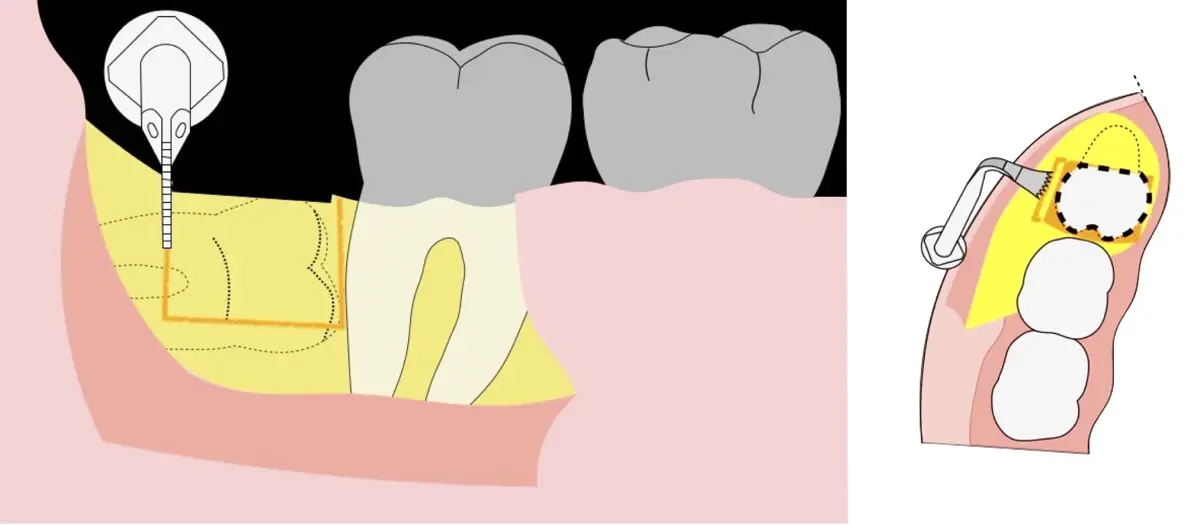

Figura 8. Odontosección mediante fresa de alta rotación y/o inserto de corte de piezoeléctrico. Posteriormente se procede al ensanchamiento del espacio pericoronario con el periótomo de piezoeléctrico para facilitar la avulsión de la pieza dentaria.

Figura 9. Avulsión de la parte coronaria de la tercera molar.

Figura 10. Tracción mesial del remanente dentario utilizando botadores en bandera.

Figura 11. Avulsión del remanente radicular de la tercera molar.